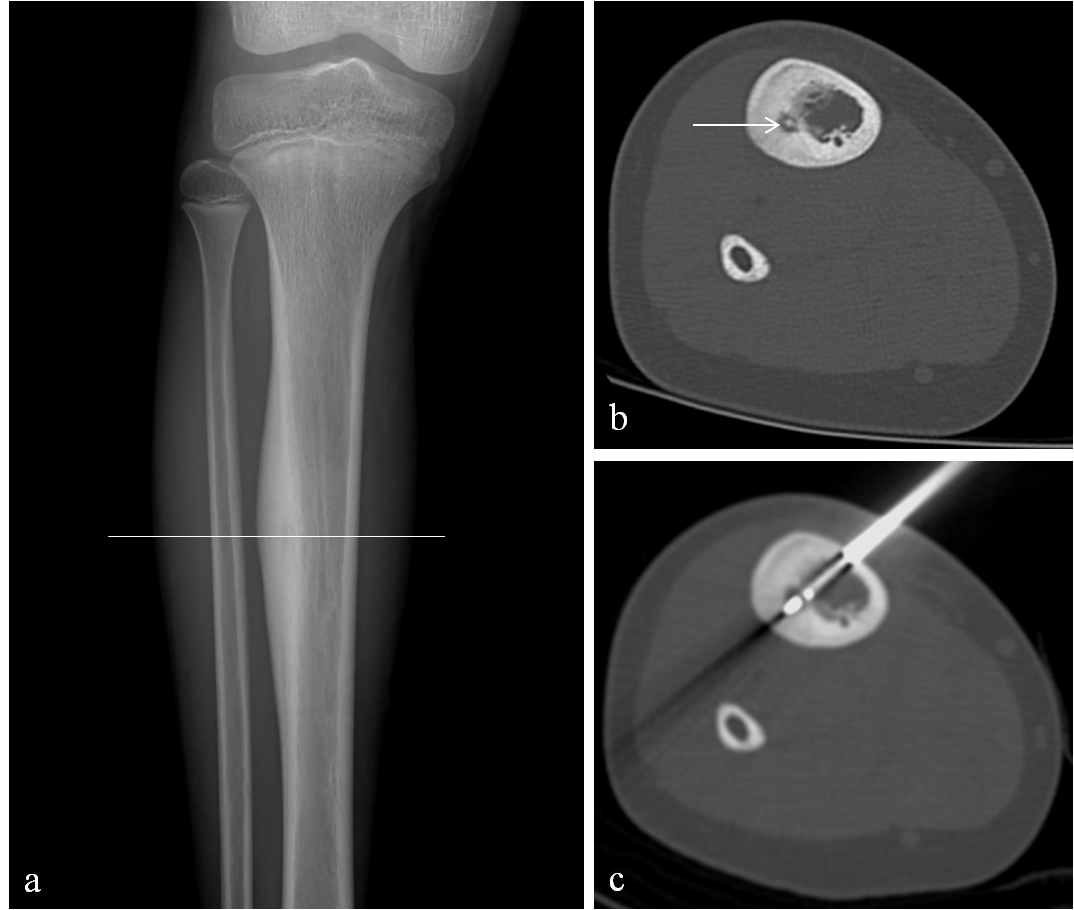

Osteoid osteoma is a benign lesion of bone, typically involving children and young adults between 5-25 years old. Despite its benign histologic nature, patients with osteoid osteoma often present with significant dull aching pain and discomfort which may worsen and become severe, especially in the evening. Unfortunately, many patients suffer with this pain for years before either seeking medical care or receiving the correct diagnosis. After clinical assessment, diagnosis is often made on radiographs as a focal area of reactive cortical thickening and sclerosis with a small central lucent nidus (Fig 1a). Occasionally, CT is required to confirm the diagnosis and can be helpful for pre-interventional planning (Fig 1b).

2). CT scan is used to target the lesion using a coaxial drill needle system that enables tissue biopsy.

3). Next, the appropriate radiofrequency probe will be advanced into the lesion which is heated at 85 to 90 degrees Celsius for 6 minutes (Fig 1c).

Figure 1: 10-year-old boy with right tibia osteoid osteoma (OO). (a): Right leg radiograph demonstrates reactive cortical sclerosis. (b): Axial CT image obtained through the right tibia at the level of the cortical sclerosis (white line in a) demonstrates the OO nidus (arrow) prior to advancing the RFA electrode across the OO (c).

Figure 1: 10-year-old boy with right tibia osteoid osteoma (OO). (a): Right leg radiograph demonstrates reactive cortical sclerosis. (b): Axial CT image obtained through the right tibia at the level of the cortical sclerosis (white line in a) demonstrates the OO nidus (arrow) prior to advancing the RFA electrode across the OO (c).